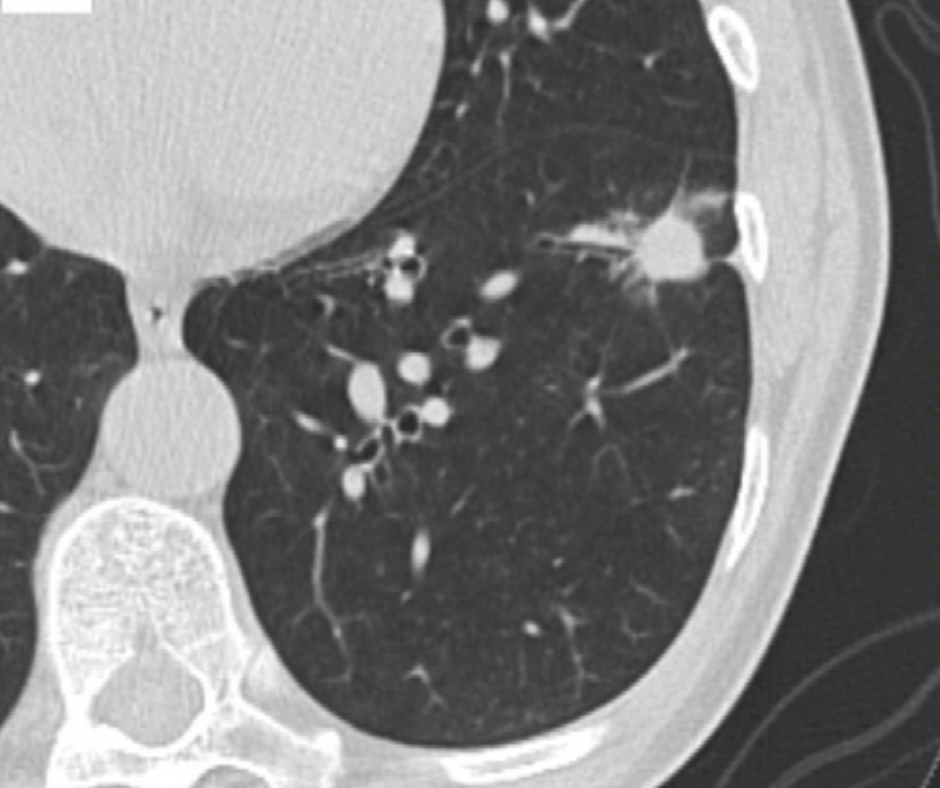

Diagnostic Imaging's Weekly Scan: May 22-May 28

Catch up on the top radiology content of the past week.

Diagnostic Imaging's Weekly Scan is your chance to catch up on the latest radiology content, from new research and device news to the latest case quizzes and conference reports. Review the slideshow below to see this week's top content: